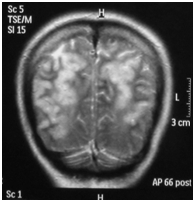

A Computed Tomography (CT) scan of the brain without contrast was done which showed low attenuation areas in bilateral parieto occipital regions with effaced subarachnoid spaces. Magnetic Resonance Imaging (MRI) of the brain depicted T2 weighted image (T2W1) symmetrical cortical high signals in the bilateral parieto occipital cortex and subcortical white matter (Figures 2) (Figure 3), suggesting Posterior Reversible Encephalopathy Syndrome (PRES). Magnetic Resonance Angiography (MRA) and Magnetic Resonance Venography (MRV) turned out to be normal.

Figure 2 (Coronal view): MRI of brain Showing T2W1 symmetrical cortical high signals in bilateral parieto-occipital cortex and subcortical white matter.

Posterior reversible encephalopathy syndrome has been reported frequently all over the world.7–9 It is a neurological condition which is diagnosed on the basis of clinical and radiological signs. The clinical features include confusion, seizures, headache and visual disturbances. Investigations such as magnetic resonance imaging usually reveal hyper intense signals at cortical and subcortical areas of posterior distribution (Figures 1) (Figure 2) but other areas such as frontal lobe, brainstem, basal ganglia and cerebellum may also be involved.10,11 There are three notable patterns of posterior reversible encephalopathy syndrome i.e. holohemispheric, superior frontal sulcus and primary parietal-occipital; all of these follow the watershed areas of distribution between major cerebral arteries.12 Although Diffusion-Weighted Magnetic Resonance Imaging (DW-MRI) is of great value in detecting infarcts early on and differentiating vasogenic from cytotoxic edema, it was not available in our hospital.13